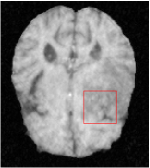

All the experiments are implemented on a Windows workstation with Intel Core i9 CPU at 3.3GHz and an Nvidia GTX-1080Ti GPU with 11GB of graphics card memory via TensorFlow Abadi et al. (2016). The parameters in the proposed network are initialized by using Xavier initialization Glorot and Bengio (2010). We trained the meta-learning network with four tasks synergistically associated with four different CS ratios: 10%, 20%, 30%, and 40%, and test the well-trained model on the testing dataset with the same masks of these four ratios. We have 300 training data for each CS ratio, which amount to total of 1200 images in the training dataset. The results for and MR reconstructions are shown in Tables 5.4 and 5.4 respectively. The associated reconstructed images are displayed in Figures 1 and 3. We also test the well-trained meta-learning model on unseen tasks with radio masks for skewed ratios: 15%, 25%, 35%, and random Cartesian masks with ratios 10%, 20%, 30% and 40%. The task-specific parameter for the unseen tasks are retrained for different masks with different sampling ratios individually with fixed task-invariant parameters . In this experiments, we only need to learn for three skewed CS ratios with radio mask and four regular CS ratios with Cartesian masks. The experimental training proceed on less data and iterations, where we performed on 100 MR images with 50 epochs. For example, for reconstructing MR images with CS ratio 15% radio mask, we fix the parameter and retrain the task-specific parameter on 100 raw data with 50 epochs, then test with renewed on our testing data set with raw measurement that sampled from radio mask with CS ratio 15%. The results associated with radio masks are shown in Table 5.4 and 5.4, Figure 2 and 4 for and images respectively. The results associated with Cartesian masks are list in Table 5.4 and reconstructed images are displayed in Figure 5.

Qualitative comparison between conventional and Meta-learning methods are shown in Figure 1 and 3, which display the reconstructed MR images of the same slice for T1 and T2 respectively, we label the zoomed-in details of HGG in the red boxes. We observe the evidence that conventional learning is more blurry and lost sharp edges, especially in lower CS ratios. From the point-wise error map, we find meta-learning has the ability to reduce noises especially in some detailed and complicated regions comparing to conventional learning.